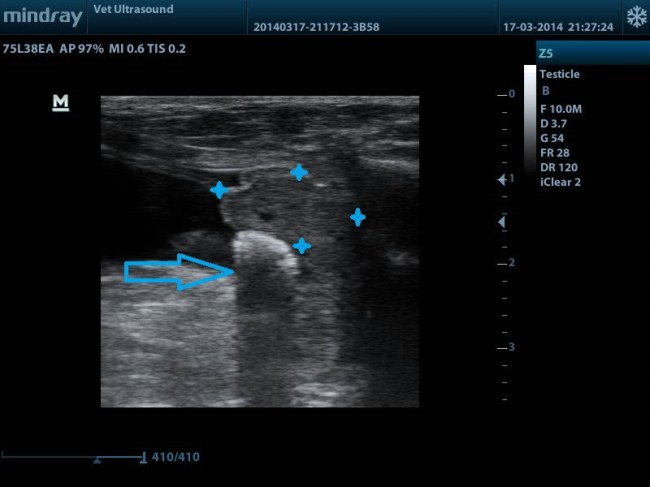

ΤΟ ΒΕΛΟΣ ΔΕΙΧΝΕΙ ΤΟΝ ΛΙΘΟ Ο ΟΠΟΙΟΣ ΒΡΙΣΚΕΤΑΙ ΣΤΗΝ ΟΥΡΟΔΟΧΟ ΚΥΣΤΗ ΚΑΙ ΛΟΓΩ ΤΗΣ ΣΤΑΣΗΣ ΤΟΥ ΑΣΘΕΝΗ ( ΟΡΘΙΑ ΘΕΣΗ) ΕΧΕΙ ΠΕΣΕΙ ΣΤΗΝ ΕΝΔΟΠΡΟΣΤΑΤΙΚΗ ΜΟΙΡΑ ΤΗΣ ΟΥΡΗΘΡΑΣ. ΧΑΡΑΚΤΗΡΙΣΤΙΚΗ ΕΙΝΑΙ Η ΣΚΙΑ Η ΟΠΟΙΑ ΦΑΙΝΕΤΑΙ ΚΑΤΩ ΑΠΟ ΤΟΝ ΛΙΘΟ ΛΟΓΩΣ ΤΗΣ ΕΝΤΟΝΗΣ ΑΠΟΡΡΟΦΗΣΗΣ ΤΟΥ ΗΧΟΥ. ΤΑ ΑΣΤΕΡΙΑ ΑΦΟΡΙΖΟΥΝ ΤΟΝ ΕΝΑΝ ΛΟΒΟ ΤΟΥ ΠΡΟΣΤΑΤΗ ΣΕ ΕΠΙΜΗΚΗ ΤΟΜΗ, Ο ΟΠΟΙΟΣ ΕΧΕΙ ΜΙΚΡΕΣ ΚΥΣΤΕΙΣ ΣΤΟ ΠΑΡΕΓΧΥΜΑ ΤΟΥ.